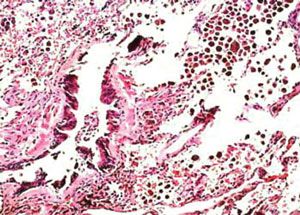

A repeated CT scan revealed persistent ground-glass infiltrates. The patient underwent a thoracoscopic biopsy. A low-power view of the specimen is shown in Figure 3.

The low-power view of the biopsy specimen shows a terminal and a respiratory bronchiole surrounded by scar tissue and alveolar septal thickening. The presence of brown pigmented macrophages abundant in the airspace adjacent to the affected bronchioles led to a diagnosis of respiratory bronchiolitis interstitial lung disease (RB-ILD).

RB-ILD was first described by Myers and colleagues1 in 1987 in their report on 6 heavy smokers who had clinical, radiological, and physical evidence of interstitial lung disease. Open lung biopsy specimens showed respiratory bronchioles with inflammatory cellular infiltration, thickened alveolar septa, and a clustering of light brown–pigmented macrophages in the airspaces.